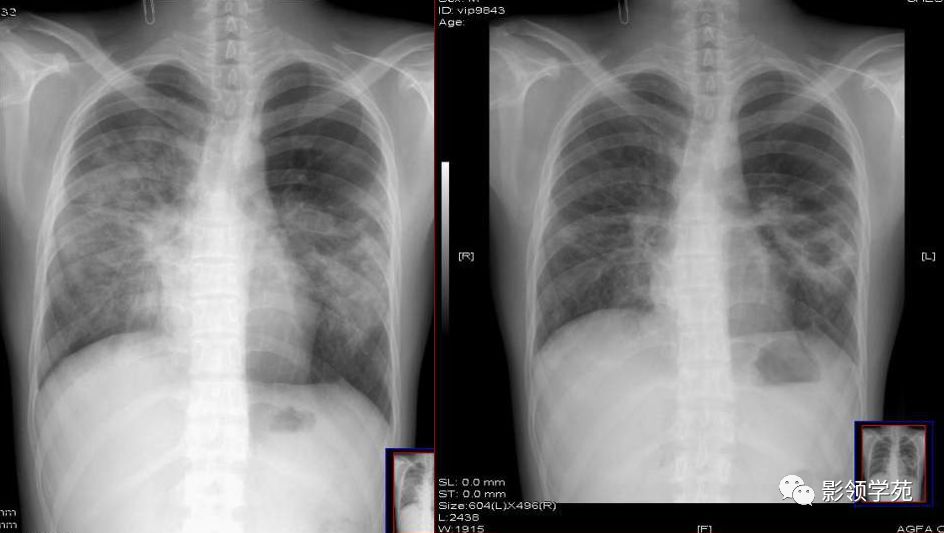

小叶性肺炎x片

图中可见右上叶"斑点花",根据公式诊断为小叶性肺炎图中可见右上叶"一

正确答案:支气管肺炎又称小叶性肺炎,常见病原菌为金黄色葡萄球菌